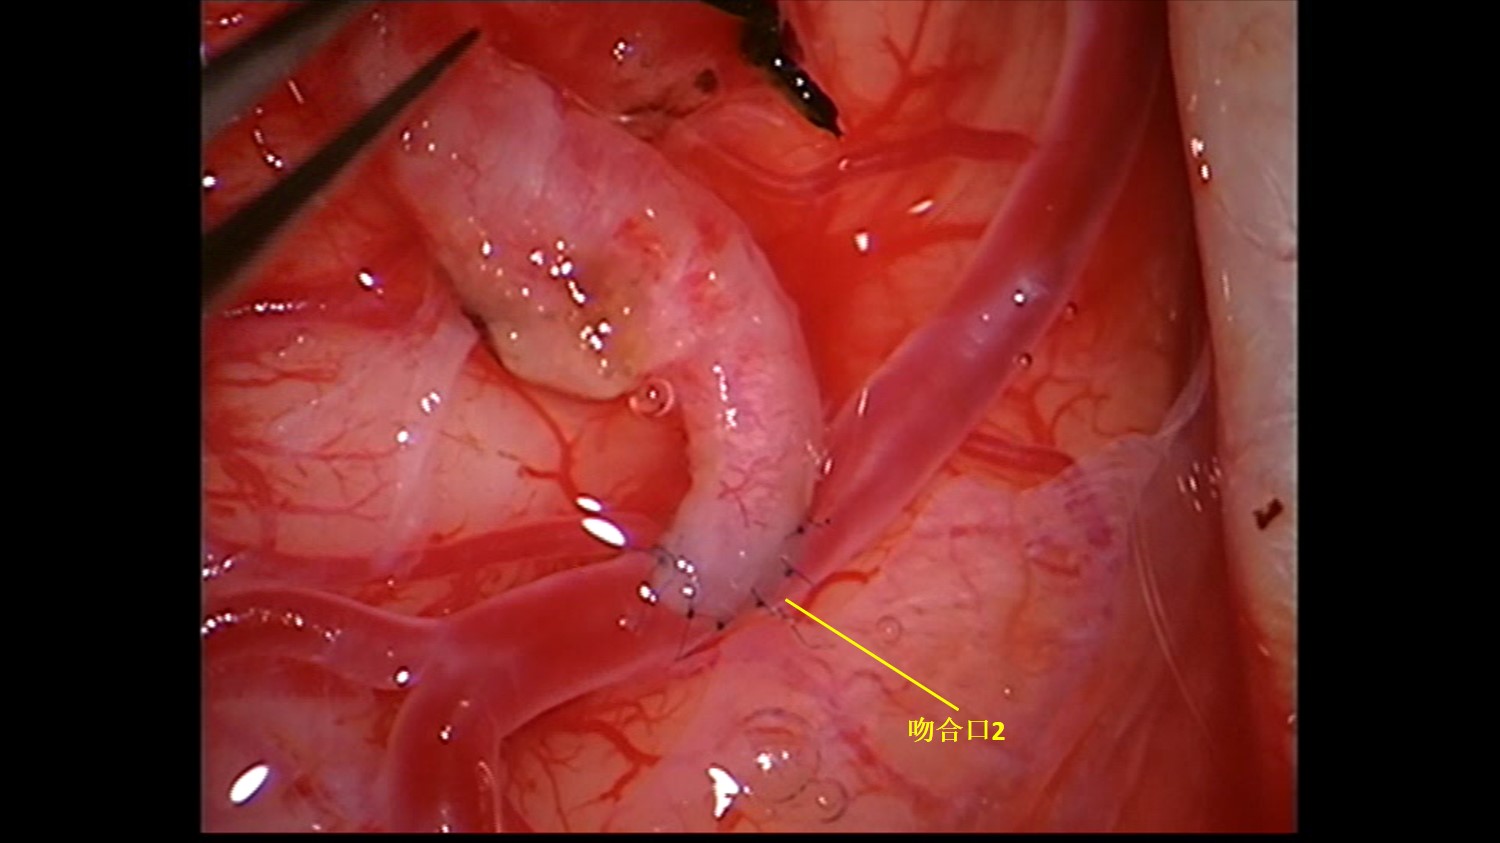

受体血管2:血流量较好,管壁薄。

吻合口2